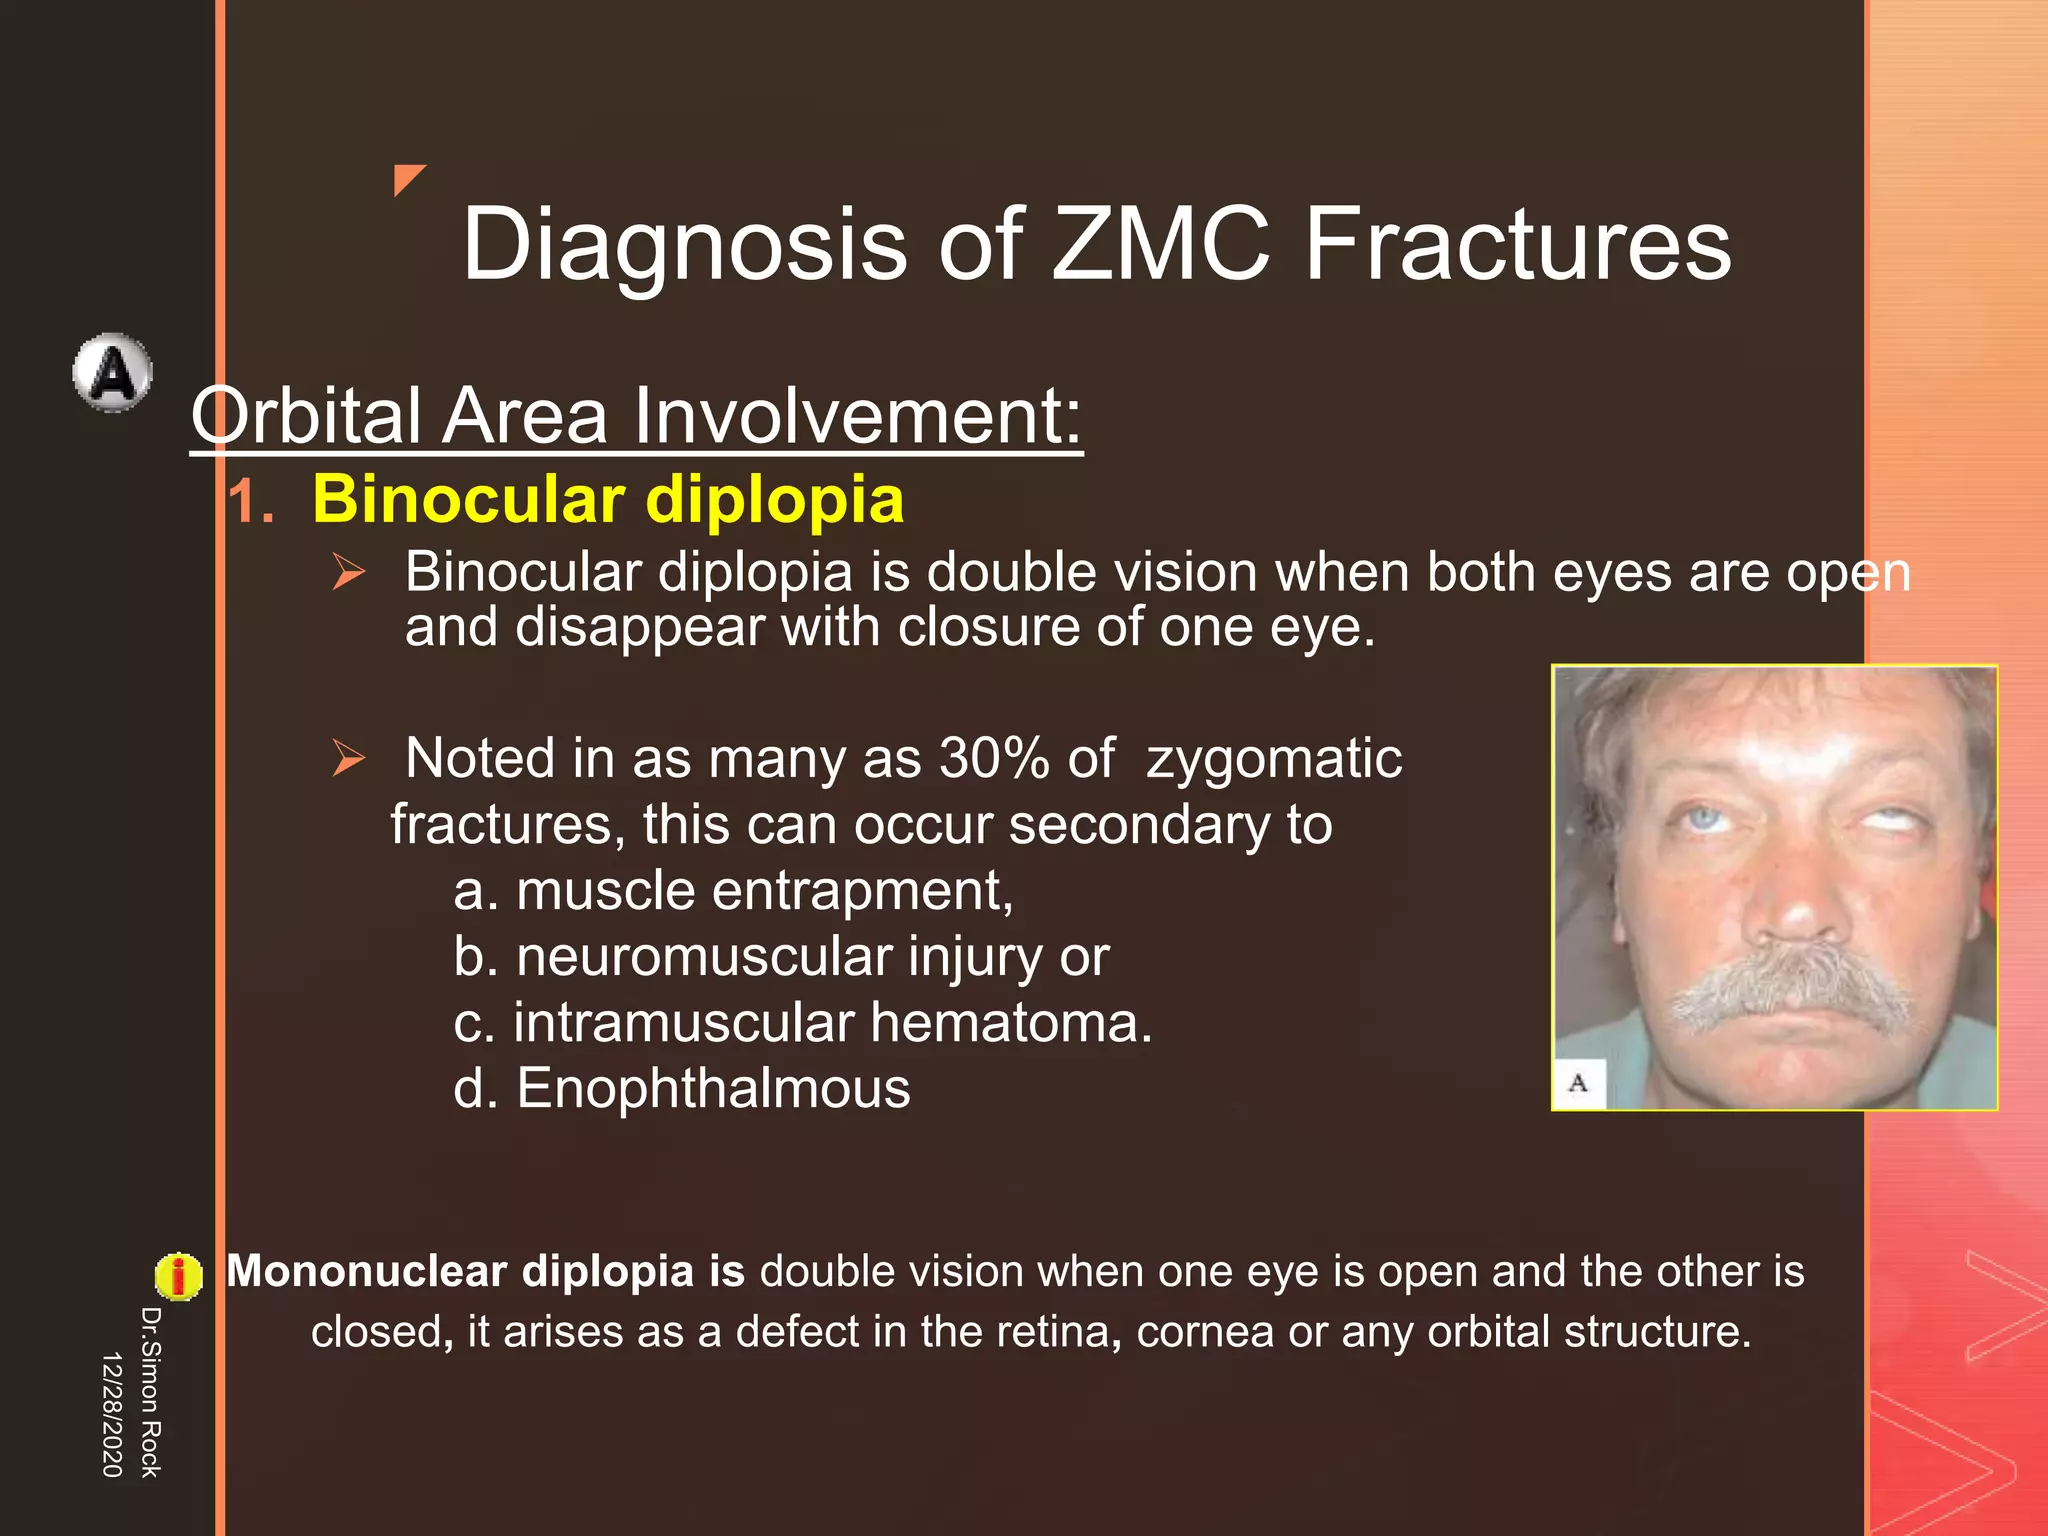

This document discusses the anatomy and fractures of the zygomatic bone. It notes that the zygoma forms the cheekbone and articulates with several other facial bones. Zygomatic fractures most commonly occur in the arch or body due to blunt trauma. Diagnosis involves checking for diplopia, ecchymosis, and other signs of orbital or facial bone involvement. Treatment may involve closed or open reduction based on the severity of displacement. Closed reduction techniques try to elevate the bone back into position without surgery, while open reduction requires surgical exposure and fixation of the fracture site.